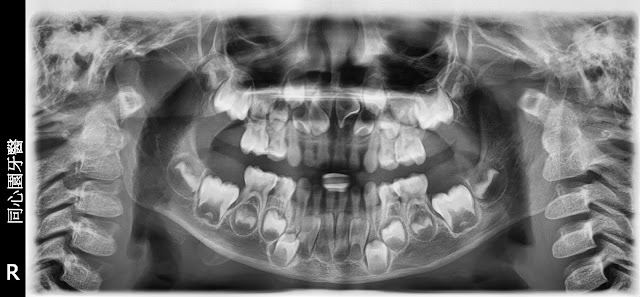

7歲(女)